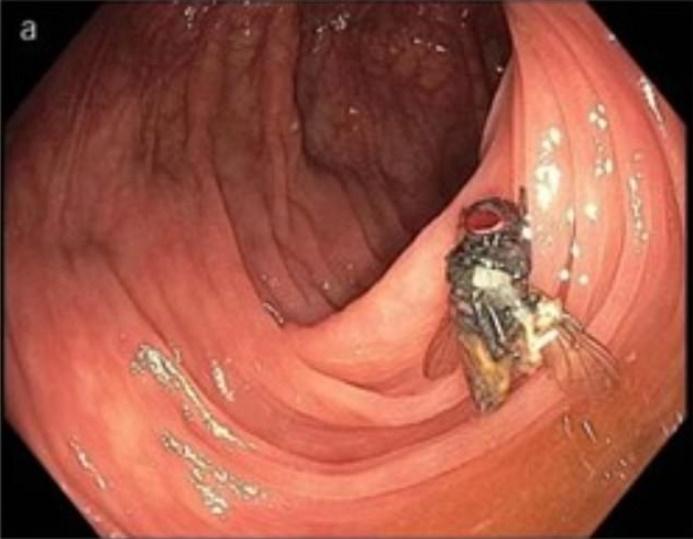

照大腸鏡其中一種常用和普及的身體檢查方法。美國密蘇里州卻出現一宗驚人病例,一名六旬漢接受例行性大腸鏡檢查時,竟然被發現腸道裡有一隻「活生生的烏蠅」,就連醫生都覺得難以置信,推測事主可能是之前吃到含有烏蠅幼蟲或卵的食物,才導致烏蠅在體內存活。

綜合報道,這名來自密蘇里州的63歲男子,今年初接受了大腸癌篩檢,醫生都會將攝影機放入腸內,檢查內部是否有病變、潰瘍或是長瘜肉等情形。然而,當醫生把攝影機深入橫結腸時,竟發現裡頭有一隻完整的烏蠅,而最令人震驚的是,牠是活生生在事主的腸道裡,令醫生驚訝不已。醫生事後向事主問診時,對方堅稱自己24小時前只有喝水,嚴守禁食規定,而且並不察覺肚子有異樣。不過,事主表示在更早之前,則吃幾塊披薩和一些生菜,因此醫生判定可能是烏蠅的幼蟲或卵殘留在食物中,經患者吃下肚後,在他的腸道內孵化成蛹,並成功長成一隻成年烏蠅。

這宗罕見案例已在《美國胃腸病學雜誌》(The American Journal of Gastroenterology)發表,案例中的醫生表示:「烏蠅究竟是如何完整地進入橫結腸中?」他指出,這種蛆蟲寄生在人類腸子裡的情況,通常是極為少見,畢竟蛆蟲需在有胃酸的環境下存活,幾乎不太可能。不過,美國疾病控制和預防中心(CDC)則表示,這些受感染者的反應盡不相同,有的人並不會有任何症狀,有些人則會出現腹痛、嘔吐和腹瀉等情形。而疾病預防中心的人員也呼籲,通常在較溫暖的月份,比較有可能把蛆蟲吃下肚,因此呼籲民眾務必把食材清洗乾淨。